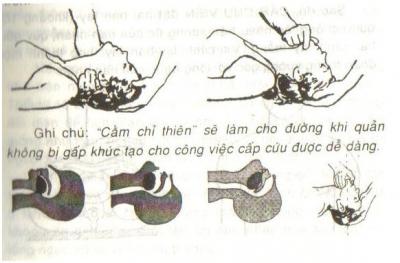

Theo quan niệm dân gian ở một số ít vùng sông nước Nam bộ, khi có trẻ bị té xuống nước thì cấm người thân, đặc biệt là cha mẹ, vớt trẻ lên, thậm chí không được “lại gần” trẻ vì “kị tuổi” với con mình, mà phải tri hô lên nhờ người khác tới cứu, sơ cứu thì trẻ mới sống được. Đây là một quan niệm không đúng, cần phài thay đổi. Quan niệm trên có lẽ do xuất phát từ tâm lý bối rối, hốt hoảng của người thân, nhất là cha mẹ khi thấy con cháu mình gặp nạn. Do đó, nếu để người thân tham gia cứu hộ, cứu nạn thì dễ “hư chuyện”. Theo nguyên tắc cấp cứu người sắp chết đuối là phải vớt nạn nhân lên khỏi mặt nước càng nhanh càng tốt. Vì nếu để nạn nhân ngưng thở quá 5 phút là não sẽ tổn thương không hồi phục. Đây là khoảng thời gian vàng, quý báu quyết định sự sống chết của con người. Chi tiết »